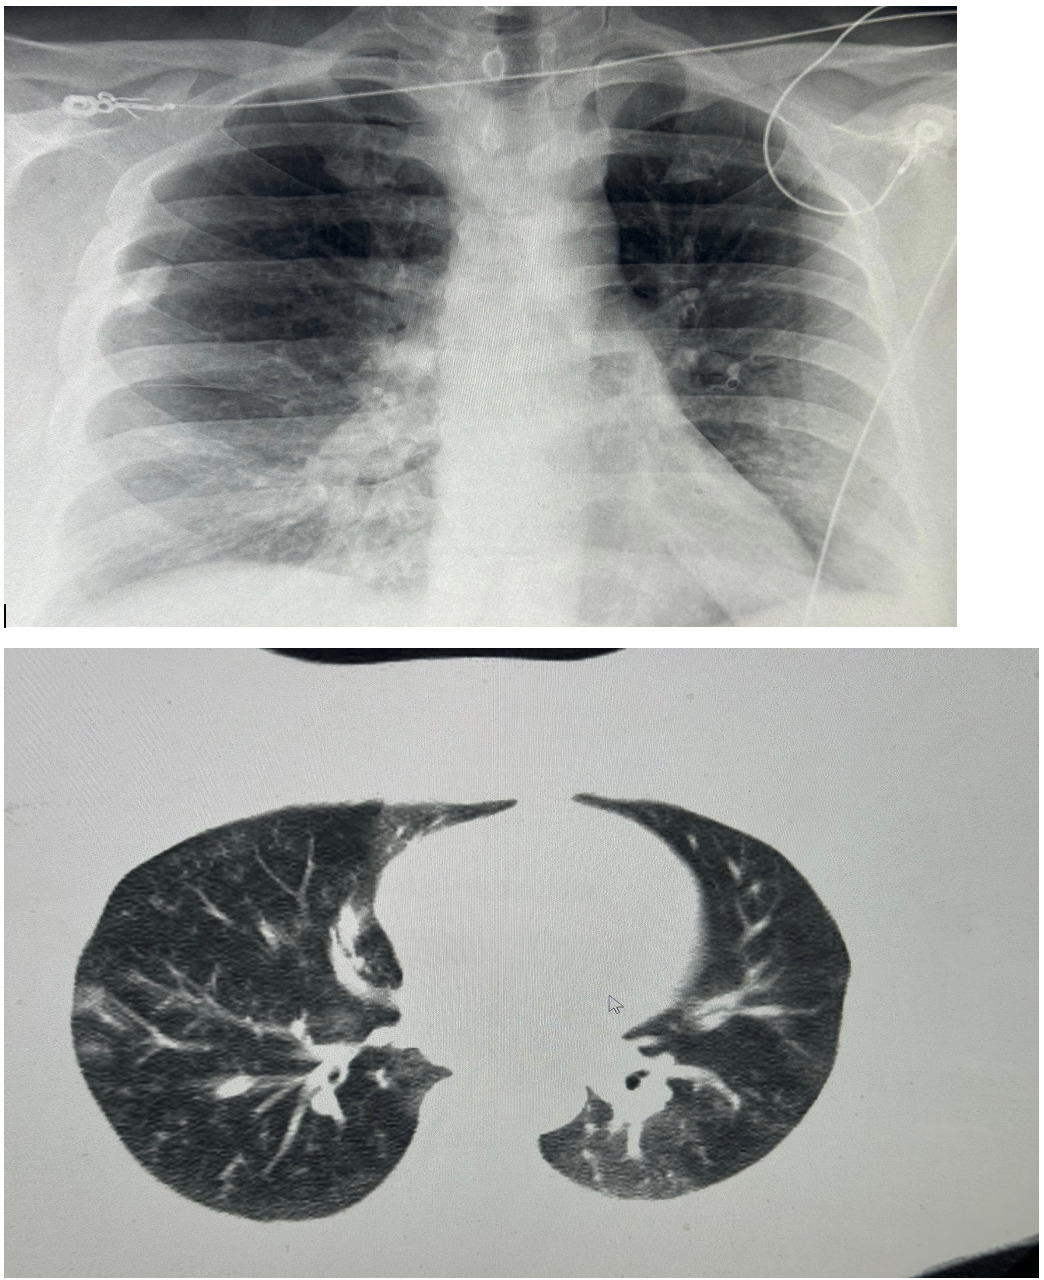

On presentation to our hospital, physical examination revealed bilateral wheezing and crackles on lung auscultation. The remainder of the examination was unremarkable. His vital signs were: blood pressure 121/70 mmHg, temperature 98.2°F, heart rate 78 beats per minute, respiratory rate 21 breaths per minute, and oxygen saturation 87% on room air which improved to >92% on 2 liters per minute of supplemental oxygen via nasal cannula. Laboratory findings were significant for mild leukocytosis (white blood cell count 12.2 x 10^9/L), with a high absolute neutrophil count (9.5 x 10^9/L) and an absolute monocyte count (1.3 x 10^9/L). His C-reactive protein (CRP) level was elevated at 264 mg/L, while his procalcitonin level was 0.08 ng/mL. HIV testing was negative. His calculated CURB-65 score was 0. Initial chest X-rays were unremarkable; However, subsequent chest CT imaging revealed a pattern characterized by small, branching nodular opacities radiating from a central line, consistent with bilateral ‘tree-in-bud’ nodular infiltrates, as shown in Figure 1. Due to persistent hypoxemia, the patient was admitted and started on intravenous ceftriaxone and azithromycin, in accordance with IDSA/ATS guidelines for CAP. A multiplex PCR on a nasopharyngeal swab was negative. However, a sputum sample yielded a positive PCR result for Mycoplasma pneumoniae on a pneumonia panel. Bacterial cultures were negative. Legionella urinary antigen and multiple fungal studies were also negative. The patient was subsequently discharged on a course of oral tetracyclines for MP-CAP and scheduled for an aortic valve replacement. The patient clinically improved.

A 32-year-old female school teacher with a past medical history significant for morbid obesity (BMI 47) presented to our hospital with complaints of cough, shortness of breath, and fever for 5-6 days. She had initially sought care at an urgent care facility where she was prescribed amoxicillin-clavulanate and initially experienced some improvement. However, her condition worsened, prompting her to present to the emergency department. On arrival at the ED, she was tachycardic (heart rate 118 beats per minute) with an oxygen saturation of 88% on room air, requiring supplemental oxygen. Her other vital signs were stable (temperature 98.3°F, respiratory rate 12 breaths per minute). Physical examination revealed bilateral rhonchi and decreased breath sounds mainly in both bases. Had mild leukocytosis on admission with a white blood cell count of 13 x 10^9/L, and a negative serum procalcitonin of 0,03 ng/ml. The chest X-ray was reviewed and reported as normal, showing no evidence of acute pathology or abnormal findings. She was admitted and initially started on intravenous ceftriaxone and azithromycin, in accordance with IDSA/ATS CAP guidelines. A nasopharyngeal respiratory panel was positive for Mycoplasma pneumoniae. IgM titers for MP were elevated, while IgG titers were negative. A subsequent pneumonia panel was also positive for M. pneumoniae, with no other co-pathogens identified. A CT of the chest showed bilateral infiltrates, as illustrated in figure 2. She was discharged in stable condition, without the need for home oxygen, after being switched to oral doxycycline to complete a 10-day course with significant clinical improvement.

Our cases are particularly noteworthy because their initial chest X-rays were unremarkable and reported as “normal”, which is atypical for MP-CAP.17 MP-CAP is often called “walking pneumonia” because it is known to cause more prominent radiographic findings than clinical signs and symptoms. However, it’s crucial to consider that radiographic findings should be interpreted in conjunction with clinical and laboratory data and that a CT of the chest may be necessary to diagnose CAP in certain scenarios if the initial chest X ray is normal and the patient presents signs and symptoms of pneumonia with hypoxemia.18